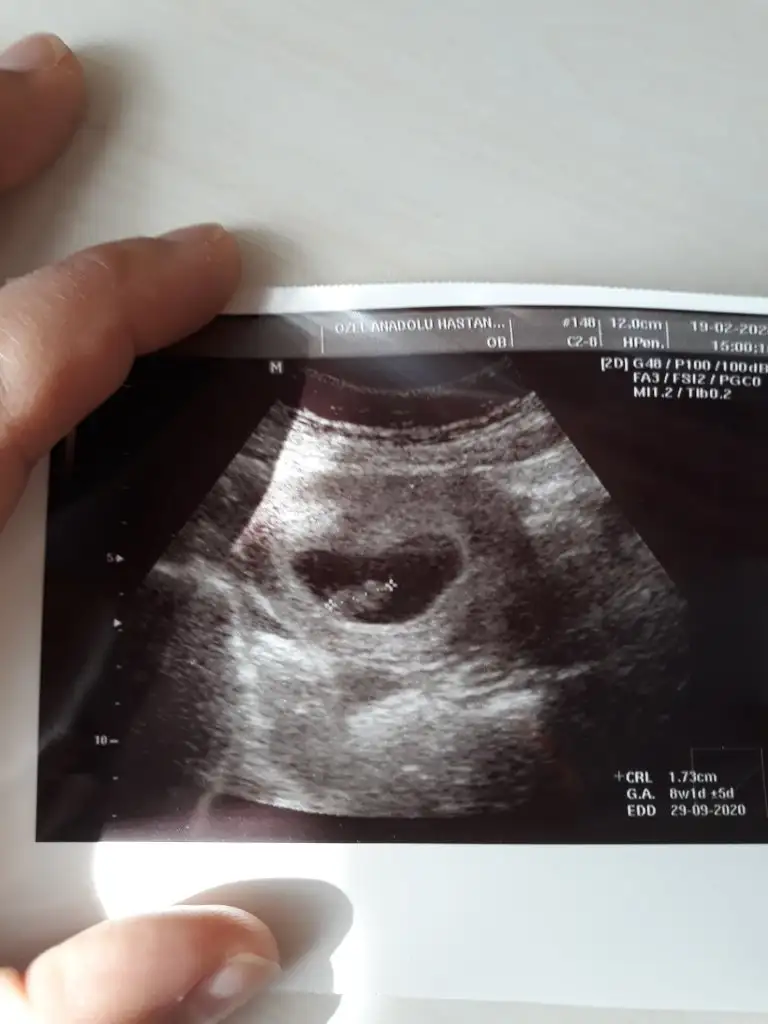

Resim çok net değil ama 8+1 günlük. Cinsiyet tahmini yapabilen varmı bebeğin kesedeki konumuna göre.